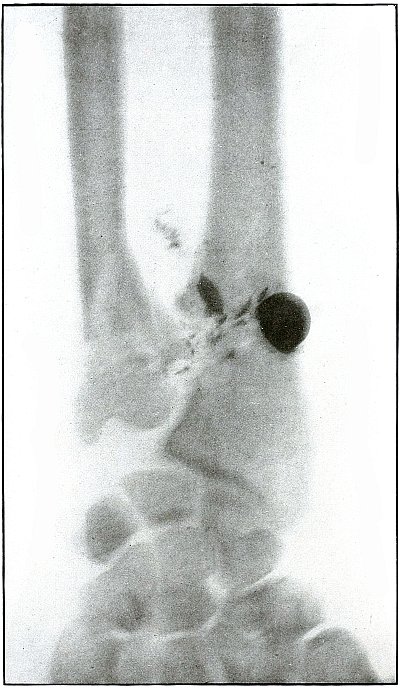

| 6. |

Gunshot wound, spinal region, lodgment of missile |

22 |

| 7. |

Gunshot wound, spinal region, lodgment of missile |

24 |